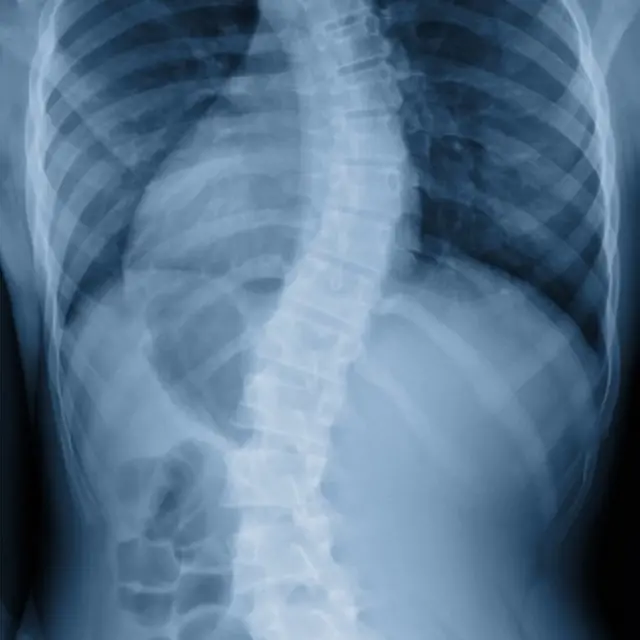

మందంగా ఉన్న పర్సును వెనక జేబులో పెట్టుకుని ఎక్కువ సేపు కూర్చుంటే నిటారుగా ఉండాల్సిన వెన్నుపాము ఆకృతి మారిపోయే ఆస్కారం ఉంటుంది. వెన్నుపాము ఆకృతిలో మార్పు నాడులపై ఒత్తిడి కలిగిస్తుంది. ఏ నాడులపై ఒత్తిడి పడితే వాటితో ముడిపడిన భాగాలకు నాడీ సంకేతాల ప్రసారంలో ఇబ్బందులు ఏర్పడుతాయి. ఇది సమస్యలకు దారితీస్తుంది.

ఇలా కూర్చోవడం వల్ల సయాటిక్ నాడి ఒత్తిడికి గురవుతుంది. సయాటిక్ నాడి నడుం నుంచి కింది భాగానికి నాడీ సంకేతాలను తీసుకెళ్తుంది. ఈ నాడి ఒత్తిడికి గురైతే నడుము కింది భాగం, తుంటి కీలు వద్ద నొప్పి వస్తుంది. అది పాదం చివరి వరకు పాకొచ్చు.